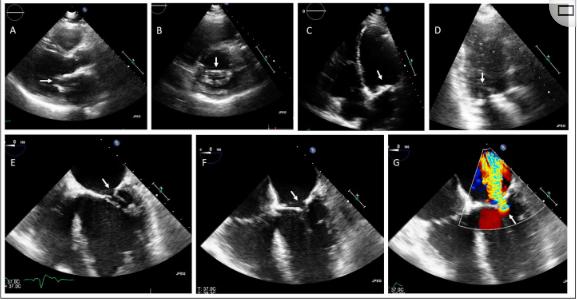

家族1的(遗传疾病研究中家系的)先证者是一名62岁的男性,因主动脉瓣和二尖瓣过早钙化和功能障碍而就诊于临床遗传学家,并有心脏瓣膜病家族史。然而,患者心血管病史始于25岁时偶然发现的心脏杂音。经胸超声心动图显示严重的主动脉瓣狭窄,为此进行了同种主动脉瓣移植术;44岁时,由于中度至重度主动脉反流,采用主动脉瓣生物假体替代同种移植物,包括主动脉根(多伦多根)。手术期间,外科医生还必须对左心室流出道(LVOT)和二尖瓣前叶进行脱钙处理。53岁时,由于二尖瓣严重钙化,出现了严重的二尖瓣反流和狭窄,为此接受了瓣膜置换(机械假体)。在同一过程中,由于中度反流,进行了三尖瓣修复。图1显示了严重二尖瓣钙化的超声心动图图像,包括瓣环和瓣叶。不幸的是,因为原生主动脉瓣在30多年前被替换了,这个瓣膜的图像无法获得。除心脏瓣膜问题外,患者心脏病史包括心绞痛和急性冠状动脉综合征背景下的冠状动脉疾病,接受了多次血运重建手术,其中在39岁第一次经皮介入手术;44岁时同时进行了冠状动脉旁路移植术。此外,患者出现左心室收缩功能降低(缺血性)、房性心律失常、左束支传导阻滞和有症状的Mobitz II型传导阻滞,具有双心室起搏器适应症。

图1、家族1先证者的经胸(A-D)和经食管(E-G)超声心动图检查显示二尖瓣狭窄,主动脉瓣生物假体(多伦多根)原位。(A)胸骨旁长轴位,(B)胸骨旁短轴位,(C)根尖4室位,(D)根尖3室位,显示严重的二尖瓣钙化(箭头)。(E)食管中部舒张期和(F)收缩期,包括(G)彩色多普勒,显示二尖瓣狭窄和反流(箭头)